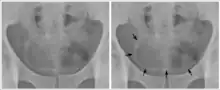

男性、女性膀胱位置